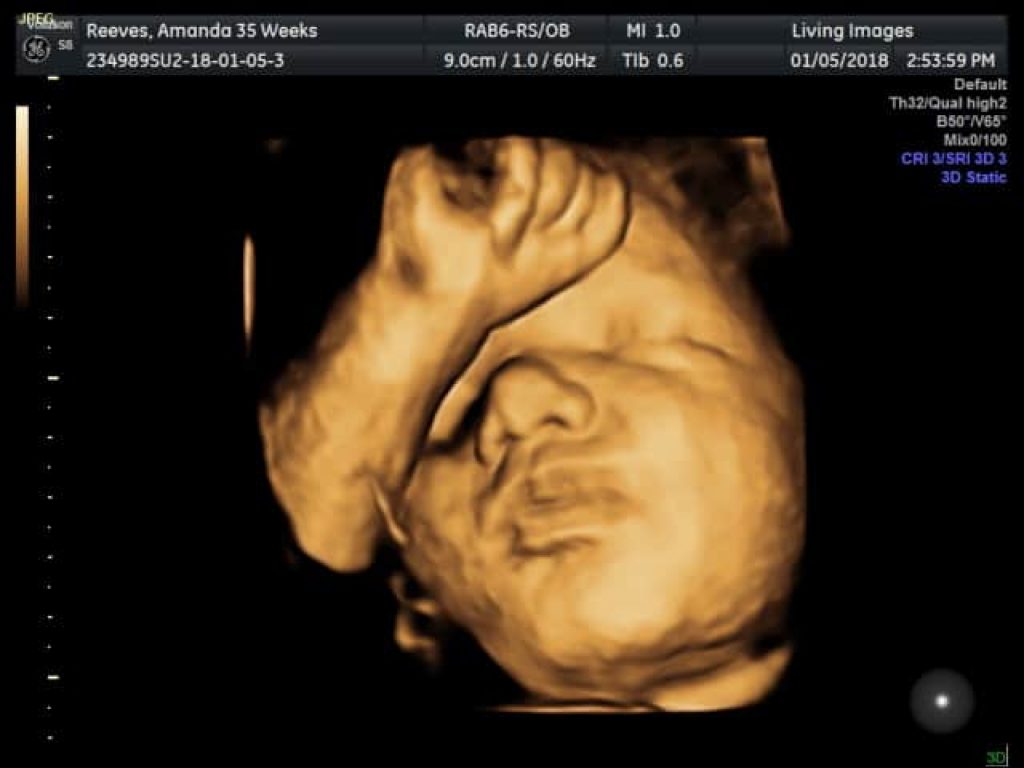

Ultrasound 3D memberikan gambar tiga dimensi yang lebih jelas.

Ultrasound 4D menambah elemen masa, memperlihatkan pergerakan janin secara langsung.

Ultrasound 5D pula menawarkan pengalaman yang lebih nyata dengan kualiti gambar yang lebih terperinci, membantu doktor dan ibu bapa melihat perkembangan janin dengan lebih jelas.